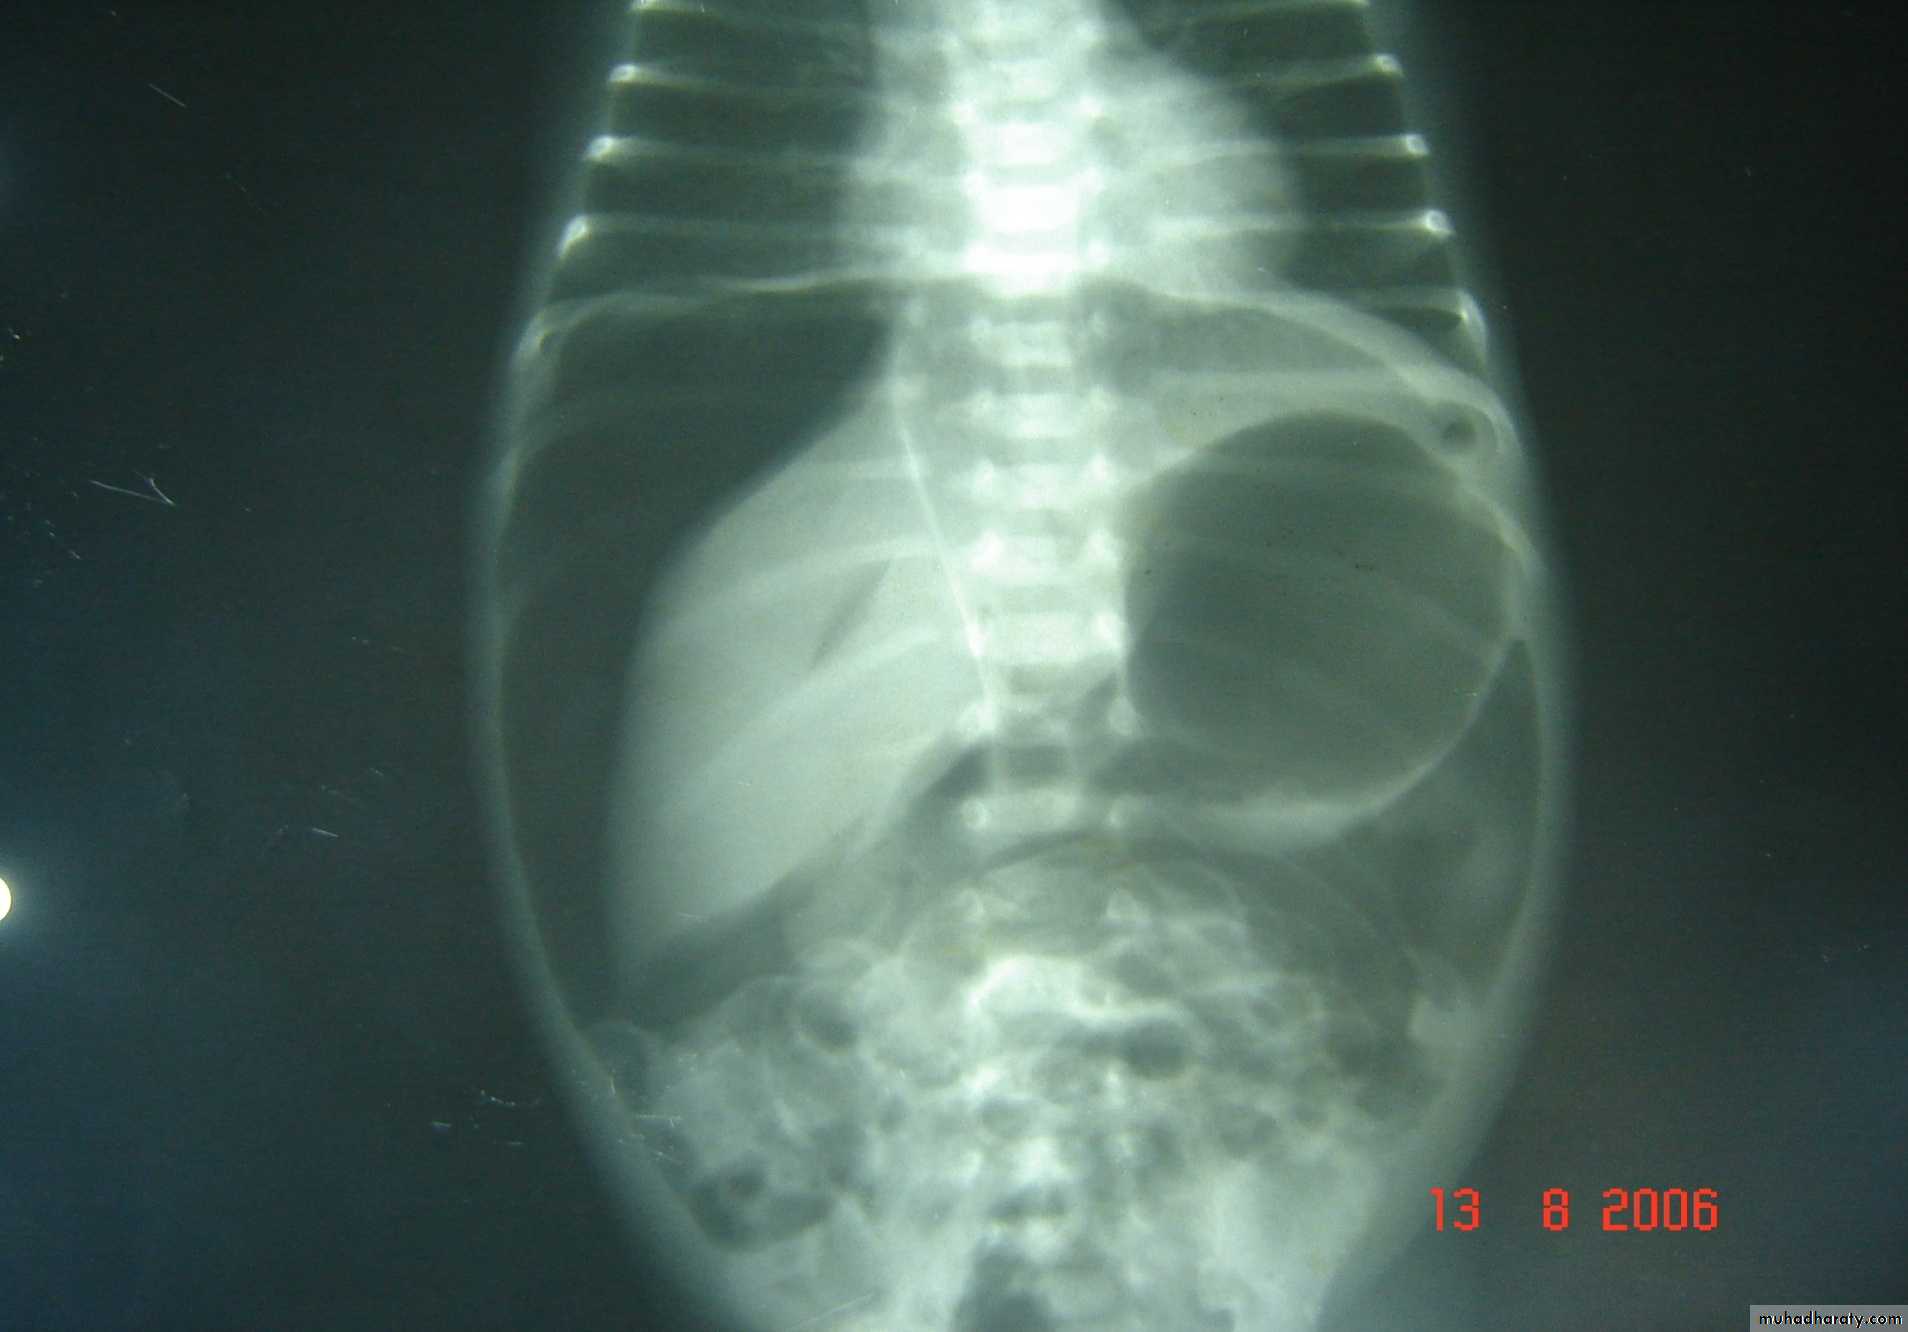

Necrotizing enterocolitis(NEC):

gastric retention (frequently bilious), distention & occult or bright red bd in stool, should raise concern. Although this disease usually occurs in premature infants, it also may occur in full-term infants.

Abdominal XR: pneumatosis intestinalis, gas in the portal vein, or free intraperitoneal gas(pneumoperitoneum) supports Dx.

GIT

pneumoperitoneum